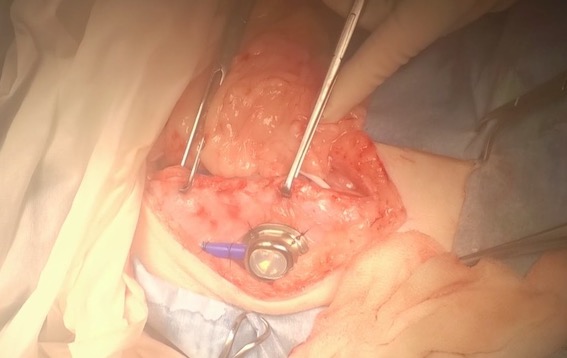

皮下に埋め込むスワールポートです。↓↓

皮下にポートを埋め込み、術後も定期的にカテーテル内部を洗浄してあげる必要があります。

手術後のSUBシステムの位置関係はこのようになります。